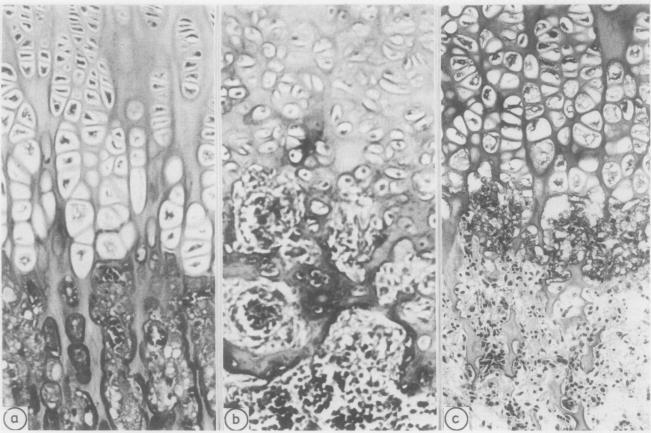

Examination of products of conception terminated after prenatal investigation.

A large number of district general hospitals have access to diagnostic ultrasonography and other methods of prenatal diagnosis, resulting in an increased supply of freshly terminated malformed fetuses to general histopathology departments, and there is now more open discussion of malformation and greater concern over fetal wastage. General pathologists are therefore under greater pressure to produce complete and detailed descriptions of a wide range of often complex anomalies. The dismissal of specimens as "multiple congenital anomalies" is becoming increasingly unacceptable to couples who wish to embark on further pregnancies and to their medical attendants. As in other fields an understanding of the methods and terminology in clinical use and a consistent diagnostic approach should help pathologists to extract sufficient information for accurate counselling.